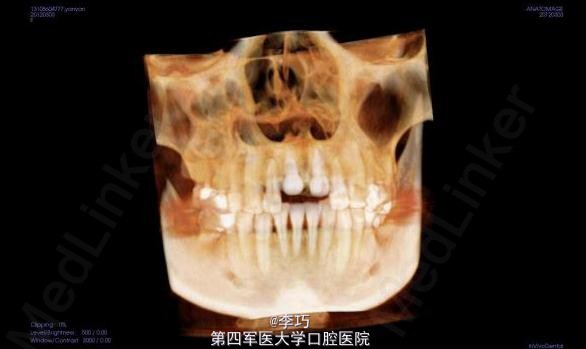

行曲面断层片和CBCT模拟植入